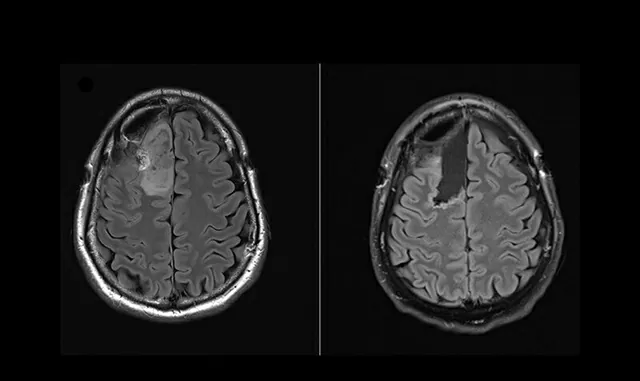

Thông qua quan sát mẫu khối u trước và sau khi dùng thuốc, nhóm nghiên cứu từ Bệnh viện Hoàng gia Melbourne (RMH) và Trung tâm Ung thư Peter MacCallum trực tiếp chứng kiến sự thay đổi tích cực trên tế bào ung thư.

Trong khi đó, bác sĩ Jim Whittle làm việc tại Trung tâm Ung thư Peter MacCallum - trưởng nhóm nghiên cứu trên - cho biết, các thử nghiệm kiểu lấy mẫu sinh thiết trước và sau điều trị để đo lường tác động vốn phổ biến ở nhiều loại ung thư khác, nhưng vì sự phức tạp của phẫu thuật thần kinh nên chưa từng áp dụng cho u não.